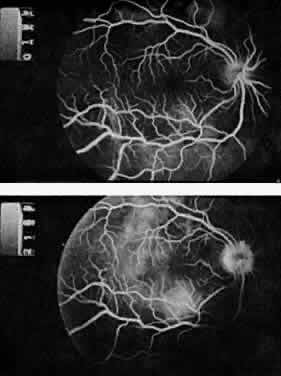

The classic ocular finding in DIC is serous retinal detachment64,65 (Fig. 5). The pathogenesis of these detachments involves choriocapillaris occlusion resulting in retinal pigment epithelial damage and subsequent loss of retinal pigment epithelial barrier and pump function. Fluorescein angiography confirms this pathophysiology, showing delayed filling of the posterior choroid with later pigment epithelial staining (Fig. 6). If the underlying DIC can be reversed, the retina may reattach, with return of vision. Other findings associated with DIC include retinal and vitreous hemorrhages.

Fig. 5. Serous retinal detachment in disseminated intravascular coagulation. (Hoines J, Buettner H: Ocular complications of disseminated intravascular coagulation [DIC] in abruptio placentae. Retina 9:107, 1989.)

Fig. 6. Delayed choroidal filling with pigment epithelial staining in disseminated intravascular coagulation. (Hoines J, Buettner H: Ocular complications of disseminated intravascular coagulation [DIC] in abruptio placentae. Retina 9:107, 1989.)